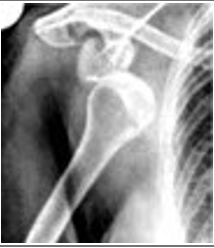

Match the correct description of the X-ray to the image.

A dislocation involving the humerus

A dislocation involving the elbow

A fracture involving the humerus

A fracture involving the clavicle